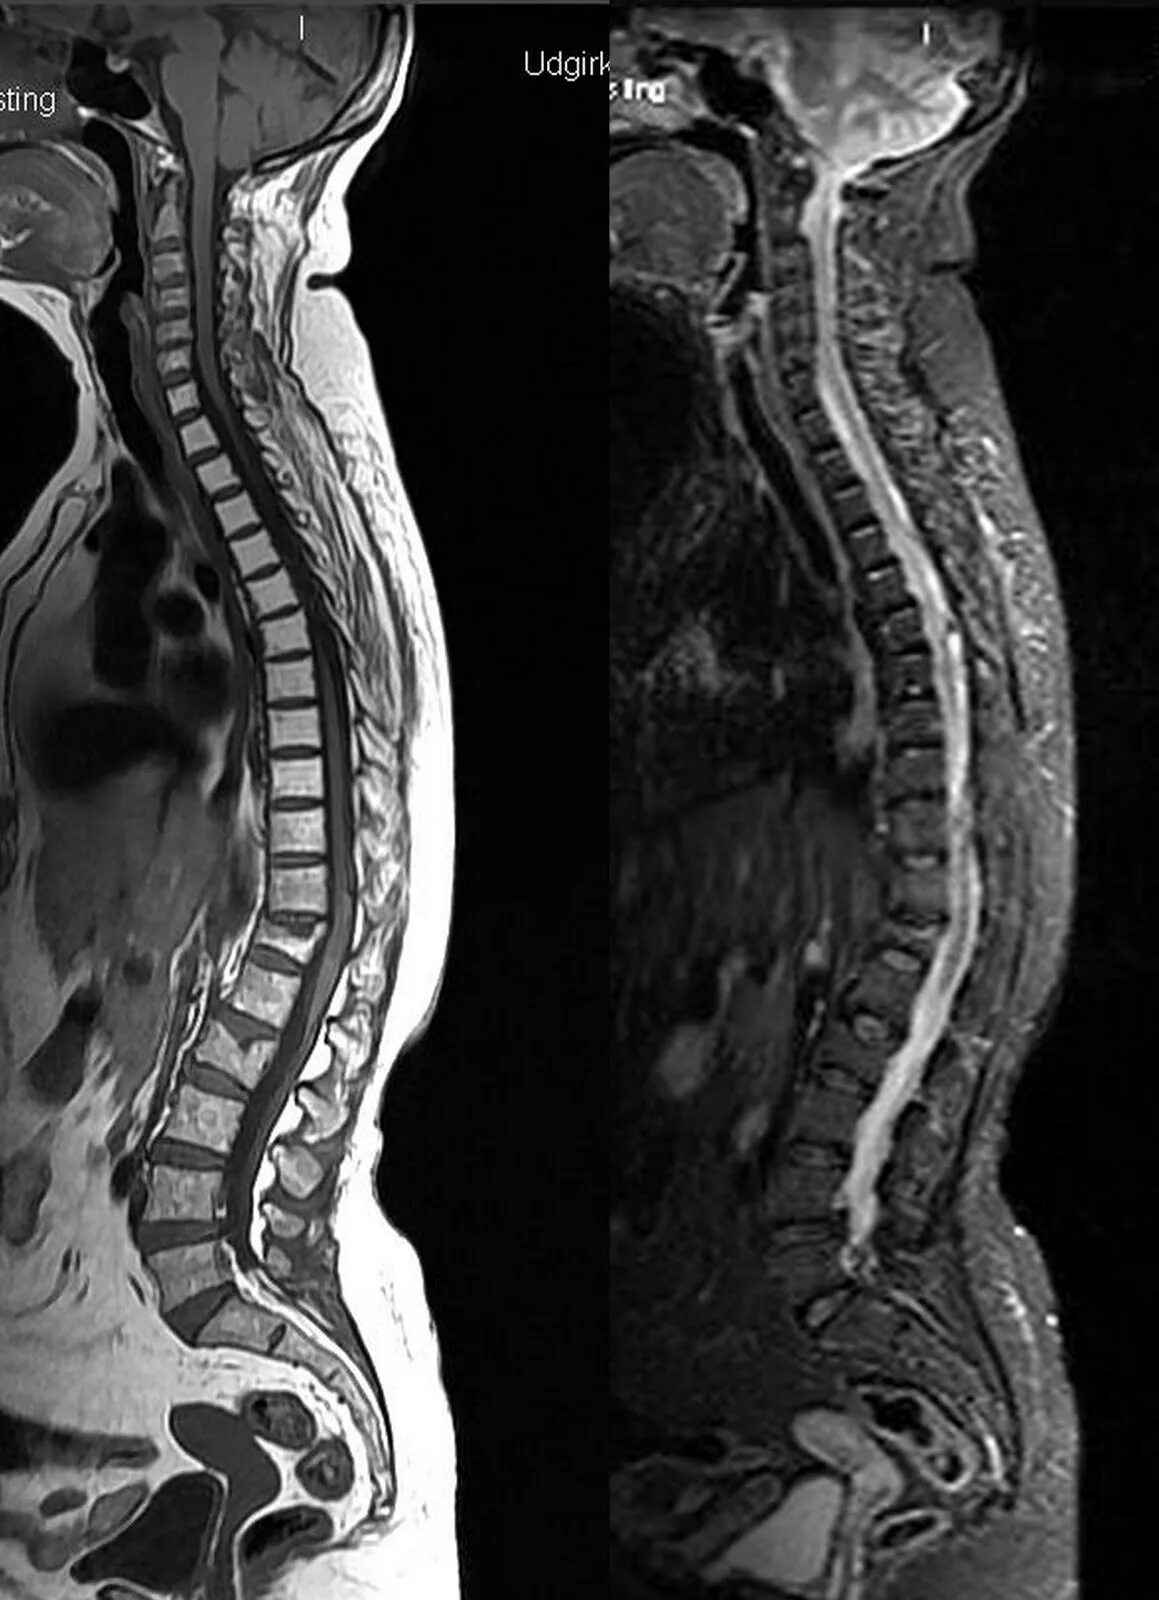

Spine mri